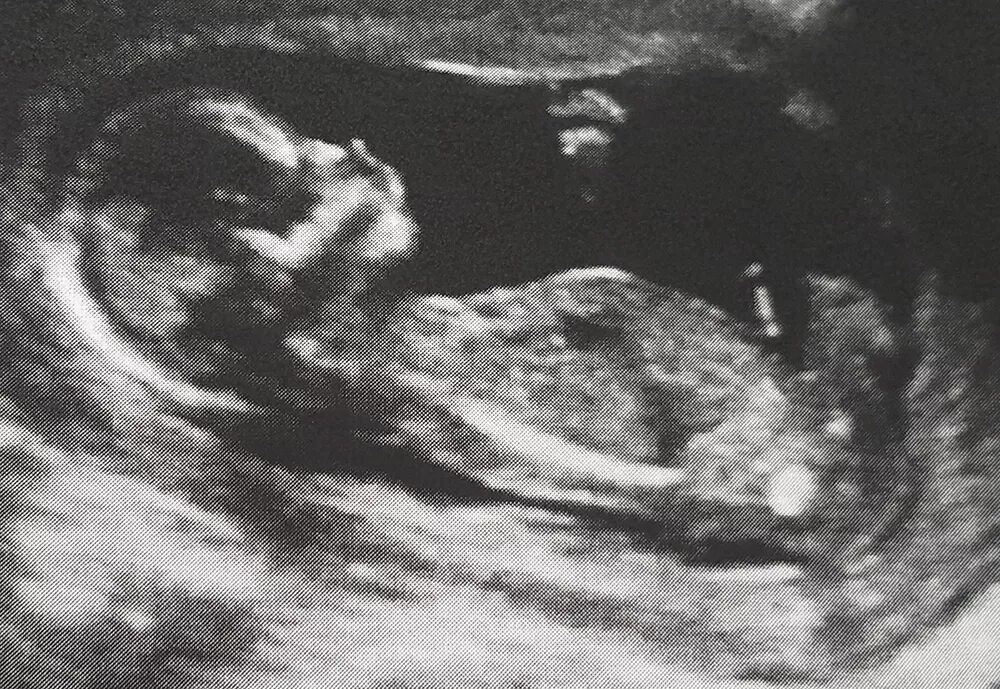

Ребенок в 13 недель